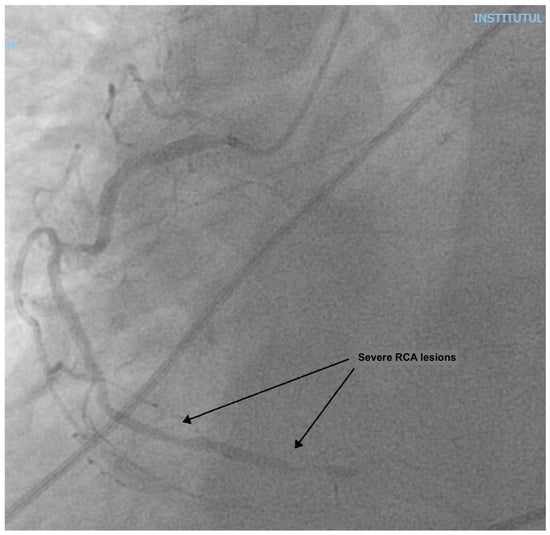

At presentation, the patient was in cardiogenic shock, at Society for Cardiovascular Angiography and Interventions (SCAI) stage C, with acute pulmonary edema: he was dyspneic, with a breathing rate of 25/min; an SpO2 of 90% under 6 L/min of oxygen, with diffuse fine crackles in both lungs; a blood pressure (BP) of 120/80 mmHg; a heart rate of (HR) 120/min; warm, but clammy skin; and a serum lactate of 2.5 mmol/L. He had a loud holosystolic murmur at cardiac auscultation. The ECG showed inferior ST-elevation myocardial infarction (STEMI), and the fast trans-thoracic echocardiography (TTE) showed moderate left ventricular (LV) dysfunction, with an ejection fraction (EF) of 40%, a moderate MR (vena contracta 6 mm), and a large VSD (2 cm), with left-to-right shunting. The patient was taken to the cardiac catheterization laboratory, where a right coronary artery (RCA) sub-occlusion was diagnosed (Figure 1), with no other hemodynamically significant coronary lesions. During the procedure, the patient was managed using non-invasive pressure-support mechanical ventilation (NIV) due to aggravated dyspnea and orthopnea. Interventional revascularization was not possible or indicated due to the distal lesions, with TIMI II flow, and the lack of benefit in an already non-viable myocardial territory. Despite significant PAD of the left inferior limb (Figure 2), an intra-aortic balloon pump (IABP) via the superficial left femoral artery was placed immediately.

Figure 2. Peripheral angiography prior to IABP placement, showing 60% stenosis of superficial femoral artery and profonda femoris artery.